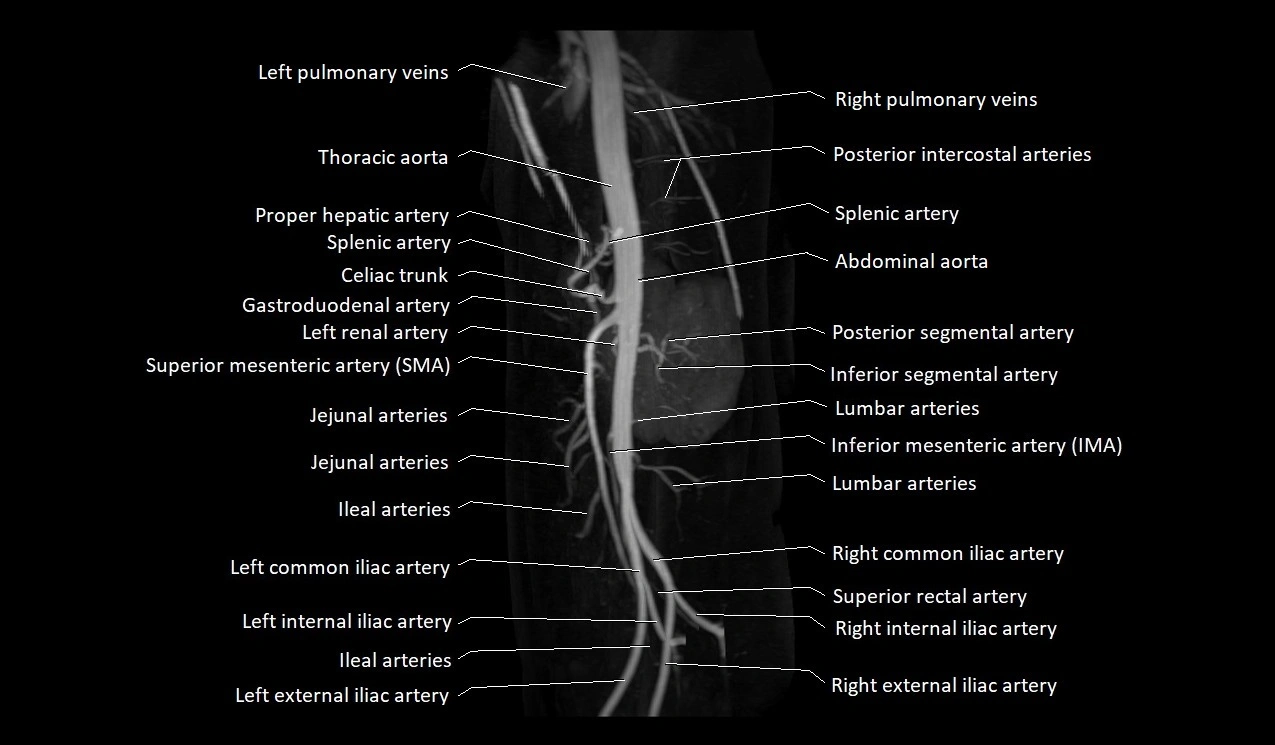

The abdominal aorta is the continuation of the thoracic aorta, beginning at the level of the aortic hiatus of the diaphragm (T12 vertebra) and terminating at the level of the L4 vertebra where it bifurcates into the right and left common iliac arteries. It lies slightly to the left of the midline and courses anterior to the vertebral bodies, surrounded by the retroperitoneal structures of the abdomen.

The abdominal aorta gives off numerous visceral and parietal branches, supplying the abdominal organs, pelvic structures, and lower limbs. It is the main conduit of oxygenated blood from the heart to the abdomen and lower body. The aorta is clinically significant as the common site of aneurysm, dissection, atherosclerosis, and traumatic injury.

Branches

• Unpaired visceral branches: celiac trunk, superior mesenteric artery (SMA), inferior mesenteric artery (IMA)

• Paired visceral branches: middle suprarenal arteries, renal arteries, gonadal arteries (testicular or ovarian)

• Parietal branches: inferior phrenic arteries, lumbar arteries, median sacral artery

• Terminal branches: right and left common iliac arteries

MRA (Magnetic Resonance Angiography):

• Contrast-enhanced MRA provides high-resolution imaging of the aorta and its branches

• Allows 3D reconstruction of visceral, parietal, and terminal branches

• Excellent for evaluating aneurysm size, dissection flap, stenosis, or preoperative planning

• Non-invasive alternative to conventional angiography

MRI images

image